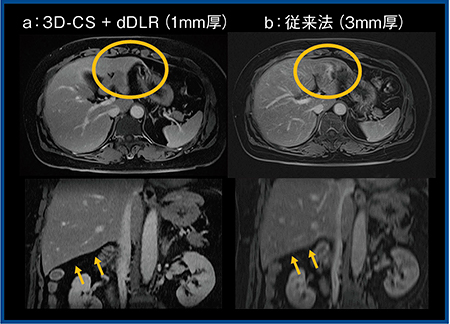

図4は腹部ダイナミックMRIで,従来法(b)では肝左葉外側区が胃と周囲の脂肪との部分容積効果によって辺縁を区別しづらいが,3D-CS+dDLR(a)では,同じ撮像時間の画像でも,空間分解能を向上できるため辺縁や肝の下面の境界も明瞭となっている。さらに,3D-CSの画像をdDLRの有無で比較すると,dDLRを適用した画像では画質が向上している(図5)。

図4 腹部ダイナミックMRIにおける従来法と3D-CS+dDLR(W.I.P.)